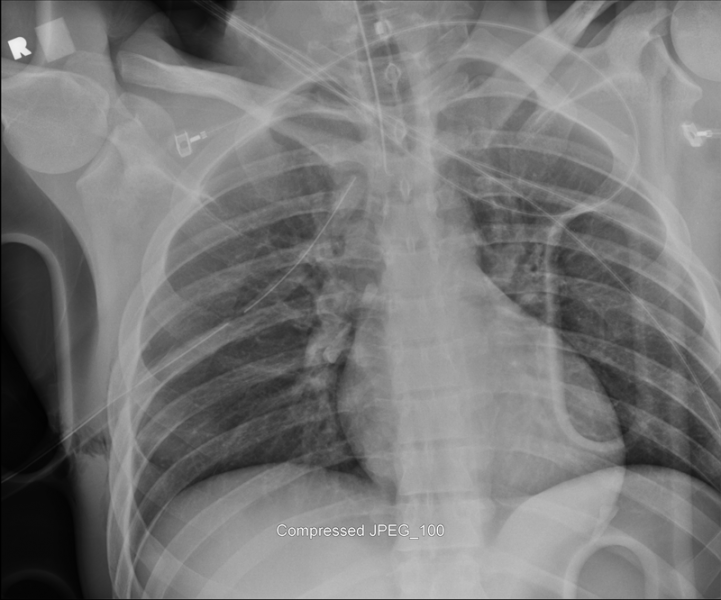

Thoracic Injuries: From Conventional X-Ray To Multidetector CT

Spectrum of lesions to be assessed in thoracic trauma Have great medical importance, social and (aortic injury) Multiple rib fractures (flail rib, CLASSIFICATION OF ... Fetch Document